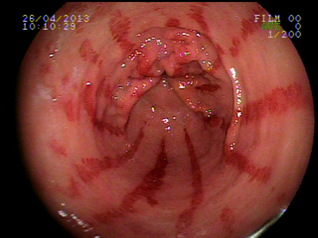

Ectasiva Vascular Antral • Endoscopia Terapeutica

Ectasiva Vascular Antral